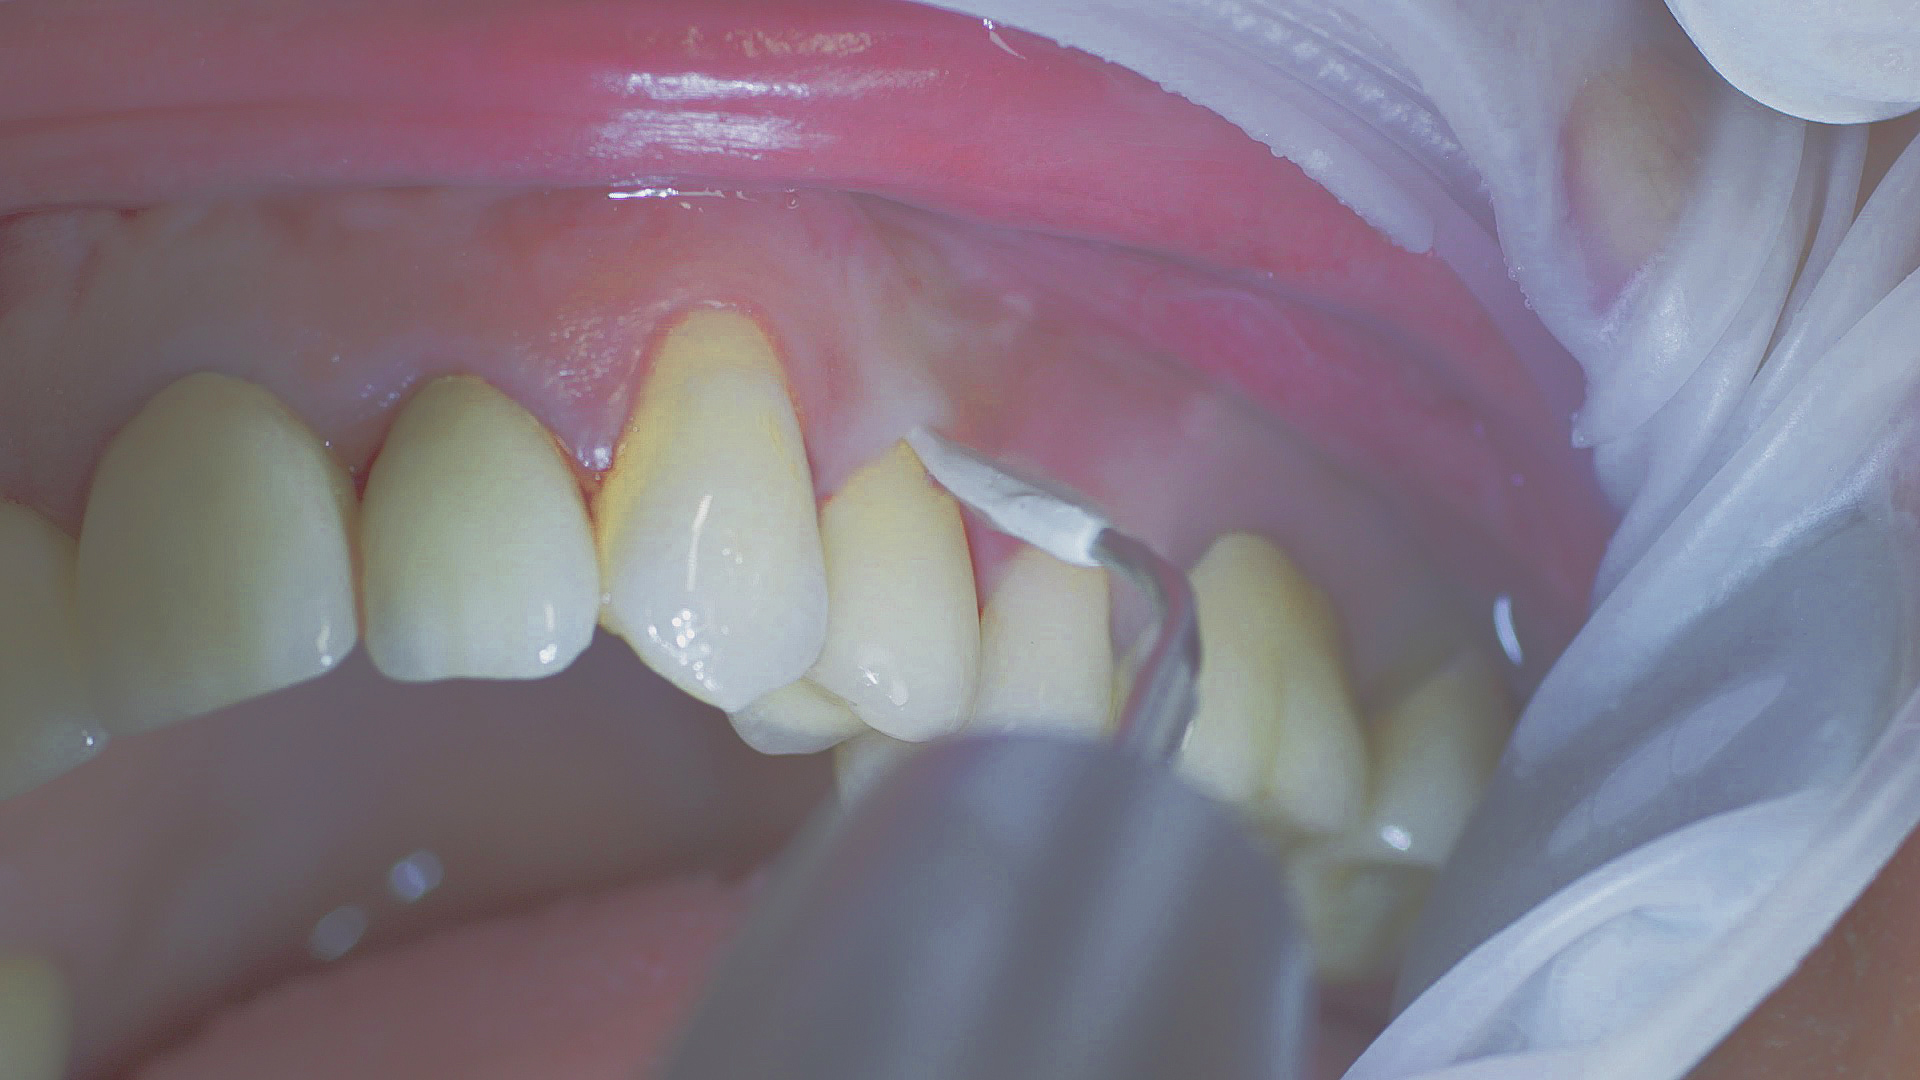

Every dental examination is based on a detailed medical history combined with targeted diagnostics con- taining as much detail as possible: The dentist records systemic risk factors such as diabetes or smoking and identifies any potential increased tendency to inflammation.[3] Hard and soft tissues are examined and periodontal pockets are probed in a screening test according to PSR (Periodontal Screening and Recording). In case of abnormal findings, the periodontal status is then re- corded and therapy is initiated where necessary. This treatment begins with professional biofilm management, by using, for example, rotary cups and polishing com pounds (Fig. 1), and comprehensive instructions in oral hygiene. Sonic or ultrasonic systems remain an effective alternative or supplement to manual instruments for sub- gingival debridement and biofilm management (presentation by Prof. Dr Ulrich Schlagenhauf; Fig. 2). Supplementary use of photodynamic therapy, air polishing or local and systemic antibiotics is not adequately documented (Prof. Dr Sema Hakki).[4] According to Dr Sergio Bizzarro, improved biomarker diagnostics may lead to an increase in customised patient therapy in the future.

Fig. 2: An air scaler efficiently performs the initial debridement, as part of initial periodontal therapy.